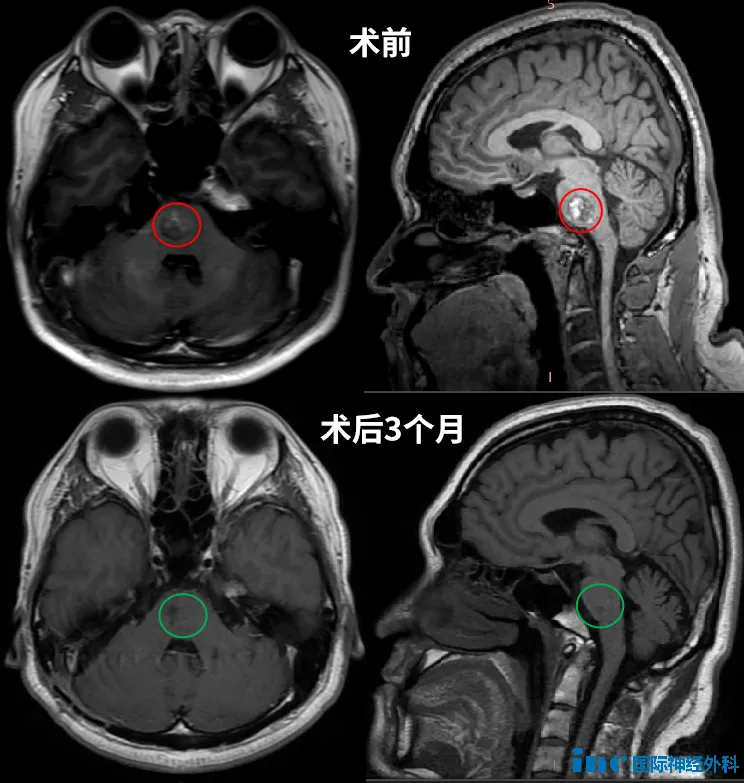

手术的核心目标是在全切病灶的同时,保护周围珍贵的神经和血管。凭借精准的术前规划和丰富的临床经验,巴教授带领团队顺利开展手术。整个过程有条不紊,每一步都精准避开神经血管密集区,最终成功将15×16×17mm的病灶完整切除。

术后第一天,当杜先生清醒过来,所有人都松了口气。他意识清晰,肢体活动完全正常,听力也没有受到任何影响。

术前最担心的面瘫、失聪等风险,统统没有出现。曾经麻木无力的肢体,也在术后康复中慢慢焕发活力,生活逐渐回归正轨。

术后1年4个月的随访中,复查核磁给出了完美结果:病灶完全切除,无残留、无复发。按照建议,杜先生下一次MRI复查将安排在2026年底,此后每三年复查一次即可。他无需特殊限制生活方式,只需像普通人一样正常生活,不必再为曾经的脑桥海绵状血管瘤忧心。